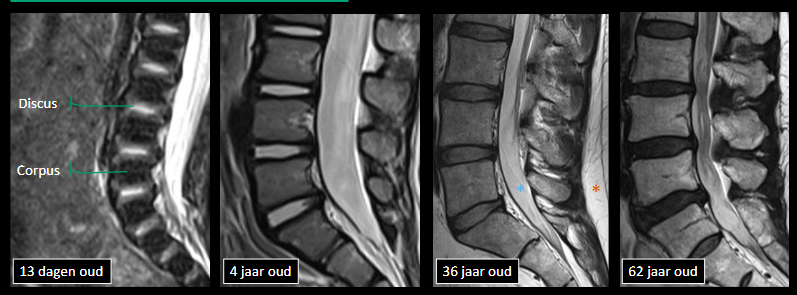

Wat kunnen we kenmerkend op MR herkennen?

Beenmerg, disci, uittedende wortels, ruggemerg, meningen, ligamenten

kenmerken T2 venster

hyperintens: vocht, vet, disci (nucleus pulposus), CSV

Welke MR-sequentie is het meest gevoelig voor het aantonen van oedeem in het ruggenmerg?

De STIR-sequentie (Short Tau Inversion Recovery) is zeer gevoelig voor oedeem, omdat vet wordt onderdrukt (hypointens) en water (zoals oedeem) hyperintens (wit) wordt afgebeeld. Hierdoor is oedeem gemakkelijk te herkennen.

Wanneer kies je voor RX, CT of MR bij verdenking van rugpathologie volgens de leerpaden?

RX gebruik je bij osteopene indeuking, controlefracturen of fixatiestatus; CT bij trauma en beoordeling van bot of discushernia; MR is de voorkeur bij hernia, tumor, myelopathie, ligamentair letsel, infectie of inflammatie van de wervelkolom.